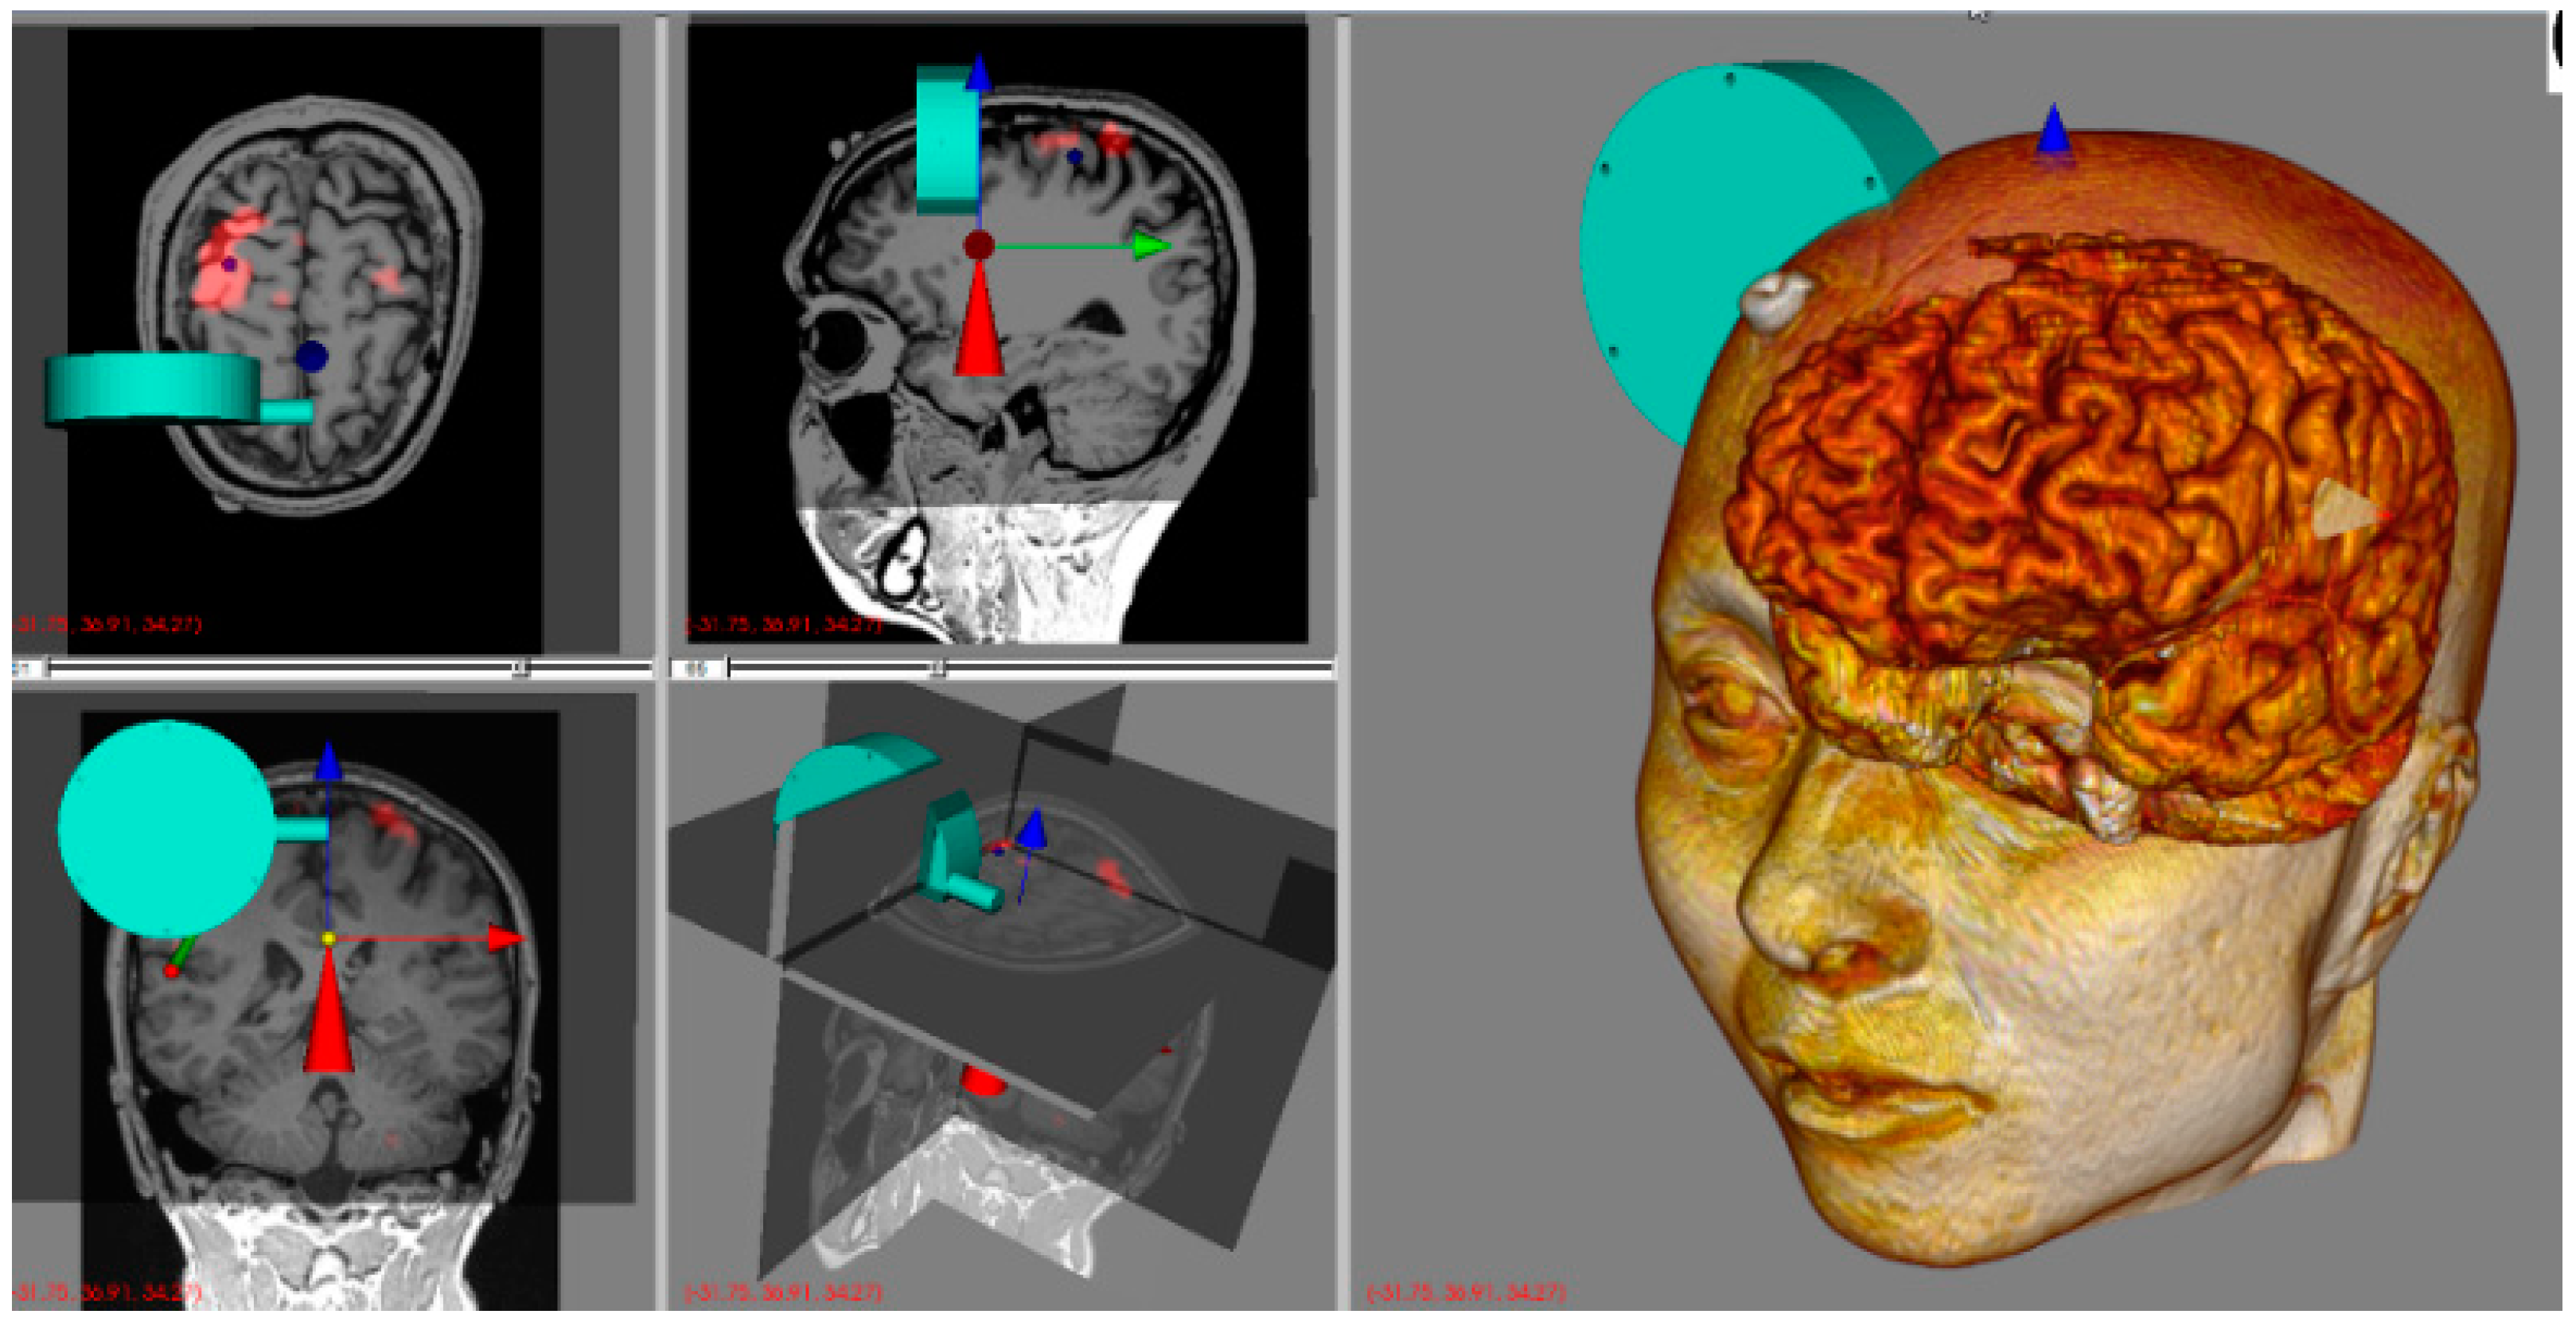

3. Spherical Robotic Positioning Device

4. Neuro-Navigation System